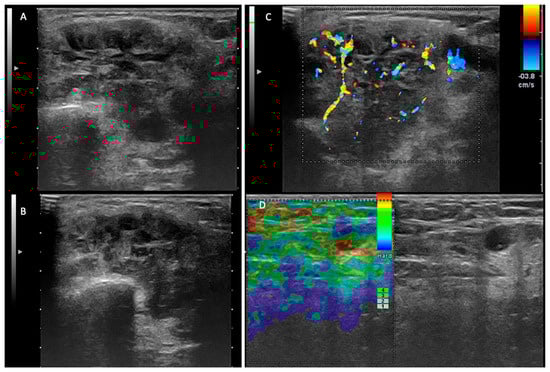

- Stoia, S.; Băciuț, G.; Lenghel, M.; Badea, R.; Băciuț, M.; Bran, S.; Dinu, C. Ultrasonography techniques in the preoperative diagnosis of parotid gland tumors—An updated review of the literature. Med. Ultrason. 2021, 23, 194–202. [Google Scholar] [CrossRef]

- Rzepakowska, A.; Osuch-Wójcikiewicz, E.; Sobol, M.; Cruz, R.; Sielska-Badurek, E.; Niemczyk, K. The differential diagnosis of parotid gland tumors with high-resolution ultrasound in otolaryngological practice. Eur. Arch. Oto-Rhino-Laryngol. 2017, 274, 3231–3240. [Google Scholar] [CrossRef] [PubMed]

- Fischer, T.; Paschen, C.F.; Slowinski, T.; Alkhameri, A.; Berl, J.C.; Klingebiel, R.; Thomas, A. Differentiation of parotid gland tumors with contrast-enhanced ultrasound. Fortschr. Röntgenstr. 2010, 182, 155–162. [Google Scholar] [CrossRef]

- Rong, X.; Zhu, Q.; Ji, H.; Li, J.; Huang, H. Differentiation of pleomorphic adenoma and Warthin’s tumor of the parotid gland: Ultrasonographic features. Acta Radiol. 2014, 55, 1203–1209. [Google Scholar] [CrossRef]

- Mansour, N.; Stock, K.F.; Chaker, A.; Bas, M.; Knopf, A. Evaluation of parotid gland lesions with standard ultrasound, color duplex sonography, sonoelastography, and acoustic radiation force impulse imaging—A pilot study. Ultraschall Med. 2012, 33, 283–288. [Google Scholar] [CrossRef] [PubMed]

- Matsuda, E.; Fukuhara, T.; Donishi, R.; Kawamoto, K.; Hirooka, Y.; Takeuchi, H. Usefulness of a novel ultrasonographic classification based on anechoic area patterns for differentiating warthin tumors from pleomorphic adenomas of the parotid gland. Yonago Acta Med. 2017, 60, 220–226. [Google Scholar] [CrossRef] [PubMed]

- Białek, E.J.; Jakubowski, W.; Karpinska, G. Role of Ultrasonography in Diagnosis and Differentiation of Pleomorphic Adenomas. Arch. Otolaryngol. Head Neck Surg. 2015, 129, 929–933. [Google Scholar] [CrossRef][Green Version]